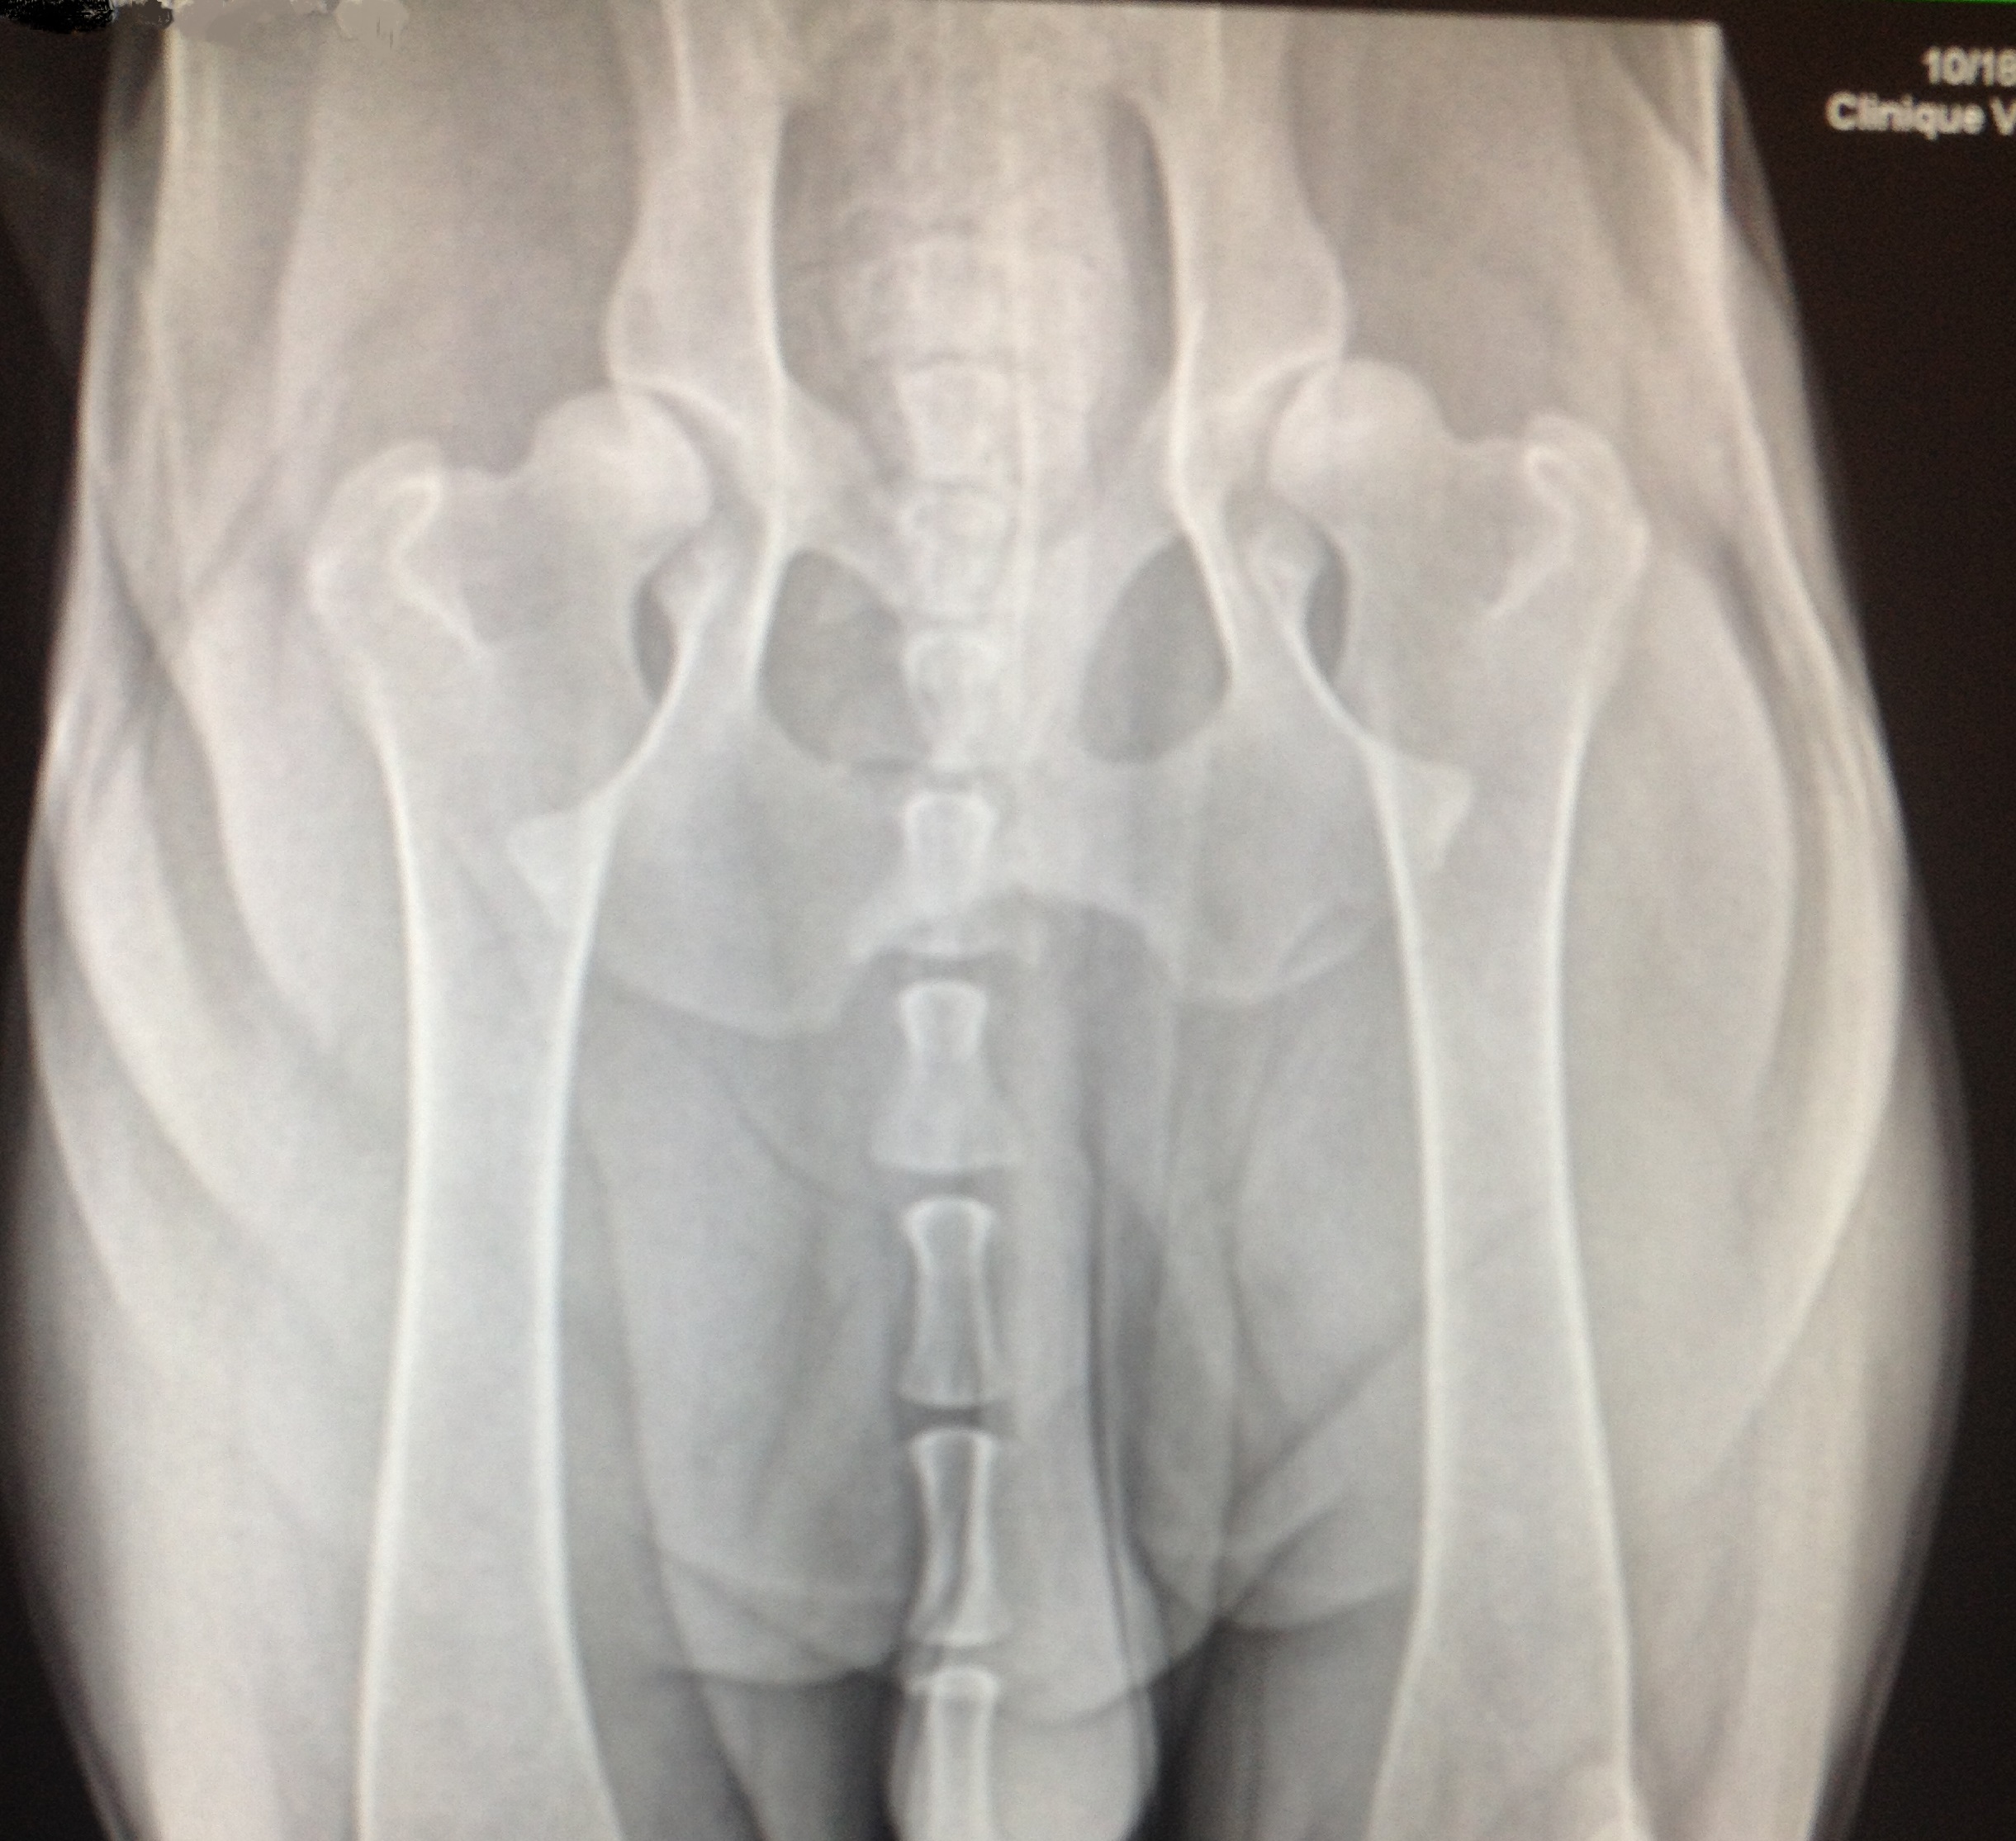

Les deux radiographies montrent des hanches avec une laxité articulaire. Ce sont les premiers signes de dysplasie. On observe souvent ce type de radiographie chez de jeunes chiens dysplasiques. Les têtes fémorales ne sont pas bien enfoncées dans l’articulation. L’espace articulaire est inégal. Les rebords osseux sont encore lisses démontrant encore peu d’ostéoarthrose, qui ne manquera toutefois pas d’arriver avec les années.